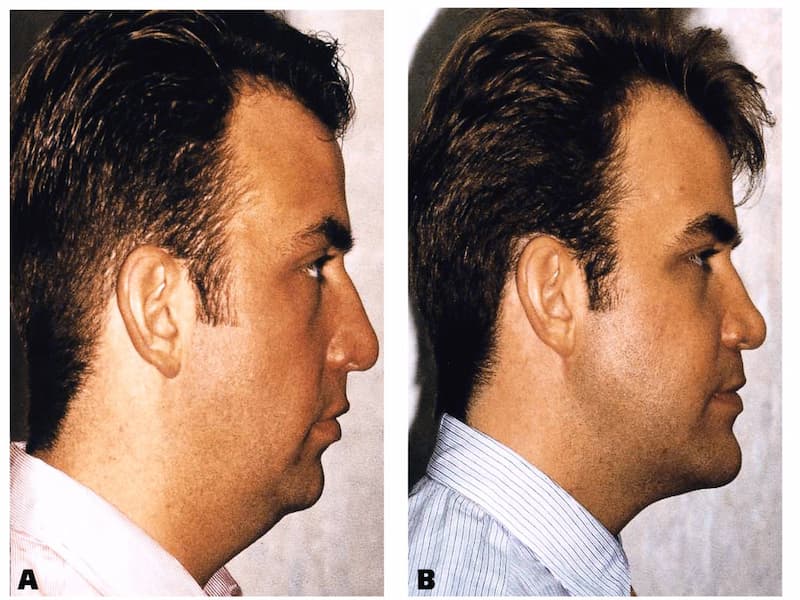

با از بین رفتن دندان های طبیعی در اثر خرابی و یا شکستگی، زیبایی چهره کاهش میابد و مشکلات جویدن و خورد کردن غذا و خوراکی ها نیز به وجود می آید.

ایمپلنت فوری فک پایین روشی تضمینی و بسیار مناسب جهت جایگزین کردن دندان ها می باشد.

می توان با ایمپلنت کردن دندان های خود همانند روز اول به راحتی غذا میل کرد.